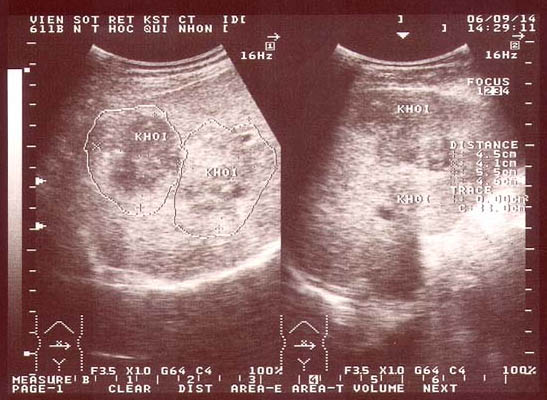

Một số thương tổn trên hệ thống gan mật qua khảo sát trên siêu âm trên hơn 1000 ca bệnh tại đa trung tâm, nhiều nhất là tại Phòng khám của Viện Sốt rét-KST-CT Quy Nhơn từ năm 2003 đến nay đã cho thấy hình ảnh thương tổn đa dạng, kích thước khác nhau và tính chất hồi âm khác nhau và có thể tổng hợp dưới đây qua thủ thuật SA bao gồm khảo sát bụng tổng quát, nhu mô gan, túi mật và hệ đường mật. Qua thăm dò, các hình ảnh bất thường liên quan đến nhu mô gan (giai đoạn cấp) là hay gặp nhất, kế đến tổn thương hệ đường mật, túi mật (giai đoạn mạn tính) với nhiều biểu hiện trên hình ảnh đa dạng, trong đó tổn thương tăng âm hình giống chiếc lá hay lưỡi liềm không kèm bóng cản (không có bóng lưng). Tổn thương nhu mô thường là vùng giảm âm phối hợp tăng âm, hoặc cả trống âm với giảm âm và tăng âm (khối hỗn hợp), trông giống như khối di căn, có bờ nham nhở không phân rõ giới hạn, tổn thương nằm cạnh TM cửa cũng chiếm số lượng không nhỏ.

Siêu âm gan mật có thể cho thấy ba loại tổn thương trong giai đoạn cấp tính. Loại tổn thương thứ nhất là hình ảnh nhu mô gan không đồng nhất, đôi khi chỉ một ổ tổn thương, chiếm chủ yếu với 86,32%, kế đến là 2 khối nối liền hoặc nằm riêng lẻ (12,09%) hoặc đa ổ (hiếm gặp hơn) không đáng kể.

Loại tổn thương thứ nhất, tổn thương hầu hết có bờ hoặc viền không rõ ranh giới giữa nhu mô lành và bệnh đi kèm tính chất tăng, giảm, hỗn hợp âm khác nhau: trong đó giảm âm chiếm chủ yếu (83,12%), tiếp đến là hỗn hợp âm (59,86%) và tăng âm (5,25%). Kết quả này cũng phù hợp với một số nghiên cứu trong và ngoài nước (Orhan S và cs., 2004; N.V. Khá và cs., 2006; M.T. Gulssen và cs., 2006; T.V. Lang và cs., 2009; A. Fica và cs., 2012). Bên cạnh các tổn thương như thế chúng tôi còn gặp một tỷ lệ đáng kể là khối echo hỗn hợp tăng âm, giảm âm kèm theo nhiều vùng trống âm (59,86%) tương tự nghiên cứu của Cosme và cộng sự (2003) và N.V.Khá và cộng sự (2006), A. Fica và cộng sự (2012).

Điều này chứng tỏ các microabces này đã hoại tử, hoặc giai đoạn vừa hoại tử vừa tiến triển có xu hướng lan rộng hoặc quy tụ thành một khối dịch lớn. Đặc biệt, các tổn thương nhu mô gan thường có nhiều “mắt nhỏ”, dạng nốt, nếu là hình ảnh giảm âm hay xen kẻ trống âm ở giữa thì thường không/ hoặc rất khó phân biệt với các dạng áp xe hay khối tân sinh ở gan (hepatic neoplasm) khi đã xuất hiện đặc điểm hoạt tử trung tâm trong nhu mô gan như một số tác giả đã từng mô tả (H.H. Quang và cs., 2005; M. Teke và cs., 2014). Song song với các tổn thương trên, nghiên cứu này có thể nhìn thấy nhiều microabces nằm rải rác trong nhu mô, thậm chí sát bao gan, xen kẻ ổ áp xe là vùng trống âm.

Kích thước ổ tổn thương thay đổi từ < 3cm đến >10cm về đường kính chiếm đa số. Với cách phân chia kích thước trung bình, số liệu cho thấy đường kính tổn thương gặp nhiều nhất và chiếm tỷ lệ cao nhất là từ 5-7cm với 466 ca (53,14%), tiếp đến kích thước từ 7 - < 10cm (23,6%) và 3 - < 5cm là 15,39%. Các khối tổn thương có kích thước > 10cm hoặc < 2cm, chiếm tỷ lệ ít hơn (5,13% và 2,74%), đối với các bệnh nhân có đường kính < 2cm này là họ đi kiểm tra sức khỏe định kỳ phát hiện hoặc họ đến sớm sau khi có triệu chứng sán lá gan ban đầu, còn kích thước lớn > 10cm mặc dù đã phát hiện và chẩn đoán trên siêu âm rồi, song vì một lý do khách quan nào đó (phụ nữ đang mang thai, thời điểm thiếu thuốc đặc hiệu triclabendazole, hoặc chẩn đoán nhầm bệnh lý khác trước khi phát hiện sán lá gan) nên họ trì hoãn quá trình điều trị đến sau sinh mới đi điều trị hoặc điều trị các phác đồ không đặc hiệu khiến cho khối tổn thương lan rộng, thậm chí nguy cơ đe dọa vỡ bao gan.